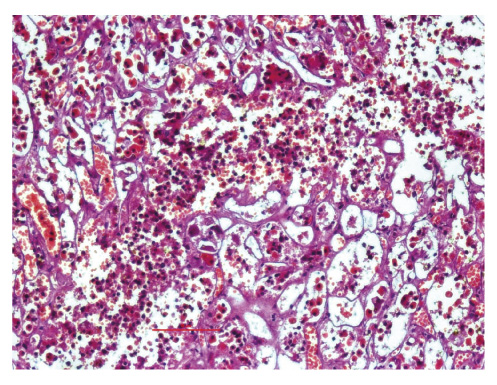

В почках наблюдаются гипоксические, метаболические и ишемические повреждения — субстрат нередко отмечаемого синдрома острой почечной недостаточности с некрозом эпителия извитых канальцев. Однако нельзя исключить специфический характер поражения почек в виде изменения эпителия канальцев почек (с обилием рецепторов АПФ2 и доказанным местом репликации SARS-COV-2), а также вариантов повреждения клубочков по типу формирующегося фокального сегментарного гломерулосклероза (коллабирующей гломерулопатии). Встречаются фибриновые тромбы в капиллярах клубочков и ишемические инфаркты вследствие тромбозов артерий почек разного калибра (рис. 12).

Рис. 12. Почка: a — некроз эпителия извитых канальцев; б — коллабирующая гломерулопатия с выпотом в полость капсулы клубочков; в — вирусное повреждение эпителия извитых канальцев; г — микроангиопатия с тромбами в капиллярах клубочков Примечание. Окраска гематоксилином и эозином, a — ×250, б — ×60, в — ×120, г — ×400.